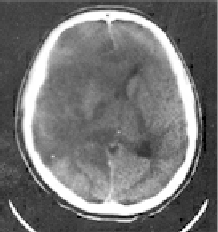

脳の腫れ

Aさんの場合、極限まで脳が腫れて、もうほんの少しで脳死となるところだった!

写真では片方の脳が著しく腫れているために、脳内の隙間がつぶれて一方に大きく片寄っている。

従来ならば脳死になっていたはずだが、低体温療法がAさんの場合、効果的だった。